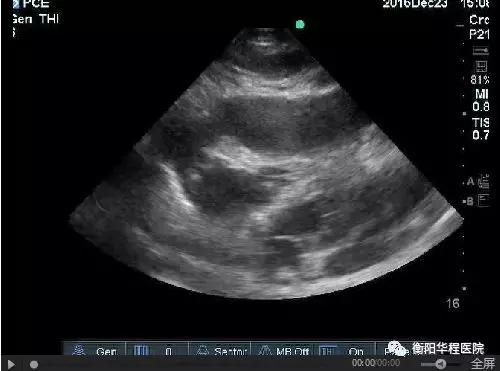

圖1 劍突下切面見大量心包積液伴右心室塌陷